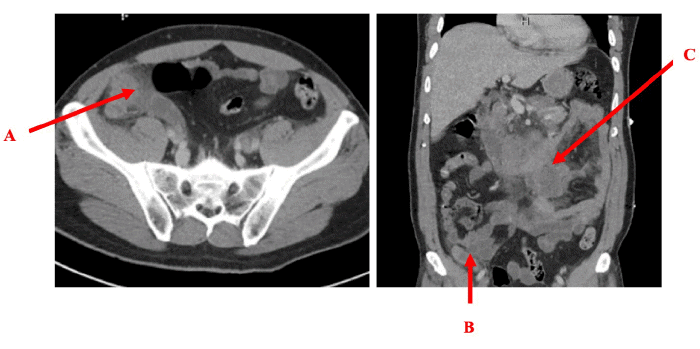

The patient underwent abdominal and pelvic CT imaging, which was significant for a moderately-sized peripherally-enhancing conglomerate of central mesenteric lymph nodes in the left central mesentery, with concerning invasion into the third portion of the duodenum (Figure 1). Additionally, the CT scan showed an enlarged appendix with surrounding peri-appendiceal stranding and a lobulated soft tissue mass in the right paracolic gutter connected to the tip of the appendix. These findings were all suggestive of potential TB involvement.

Figure 1. Abdominal CT Scan. Published with Permission

(A) Axial view showing the appendix with surrounding inflammatory infiltration (stranding) and a suspected TB abscess). (B) Coronal view of the appendix with findings similar to panel A, including stranding and a suspected TB abscess. (C) Coronal view demonstrating a mass lesion within the duodenum concerning for a TB abscess. Additionally, enlarged lymph nodes are present in the vicinity, suggestive of inflammation.